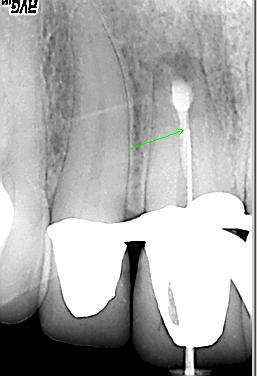

Messaufnahme

Messaufnahme nach Entfernung der oberen Guttaperchaanteile. Es erfolgt ein vorsichtiges „Herantasten“ an die Resektionsstelle. Da die Endometrie in diesem Fall keine reproduzierbaren Ergebnisse anzeigt, erfolgt die erste Messaufnahme mit deutlichem „Sicherheitsabstand“ zur Resektionsstelle (grüner Pfeil). Die Patientin ist bereits nach der ersten Sitzung beschwerdefrei.